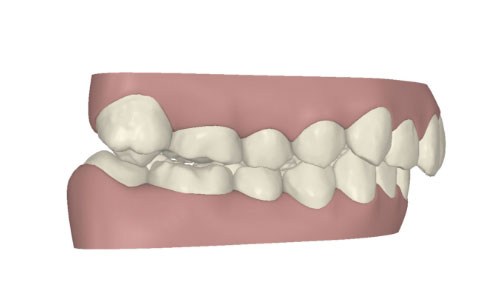

コンピューターを使って作製した透明なマウスピース型の矯正装置(アライナー)を段階的につけ替えていき、それにより歯列を矯正し、歯並びへと改善します。はじめに 治療開始から終了までのアライナーができあがってきます。マウスピース型矯正装置(インビザライン)の最大の特徴として「クリンチェック」というソフトがあります。3D のコンピュータ シュミレーション画像で、治療開始から完了までを目で見て確認することができます。

マウスピース型矯正装置(インビザライン)治療においては、クリンチェックというシミュレーションソフトを活用しております。

このクリンチェックの魅力は、治療前の現在の歯並びから治療後の歯並びを視覚化して患者様にご説明できる点にあります。

また、抜歯・非抜歯、全体矯正・部分矯正などそれぞれの治療パターンをシミュレーションすることが可能です。